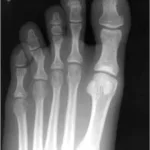

診察では, 腰部と骨盤部の圧痛を確認. お尻の筋肉を圧したときに痛みがあるほかには異常を認めず, 殿部の打撲だけかと考えました. 腰椎と骨盤のX線写真では, 明らかな骨折は認めませんでした. X線写真に写らない不顕性骨折も疑って, 腰椎と骨盤のMRIをオーダーしました. その結果, 大殿筋内に出血があり, 打撲による筋内血腫と判明. さらに第11胸椎に骨折を認めました.